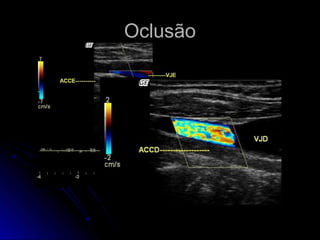

OclusãoOclusão